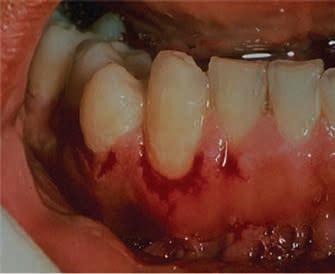

Lichen planus presents in various forms in the mouth including reticular, plaquelike, papular, atrophic, ulcerative, and bullous forms. Lesions range from asymptomatic, white lacy lines (Wickham’s Striae) in the reticular form and dense thickening of the mucosa in the plaque-like form to erythema and ulceration in the atrophic and ulcerative forms. In the former, patients may complain of sensitivity to spicy, acidic, and rough-textured foods as well as difficulty with oral hygiene (Figures 1,2).

Figures 1 and 2. Lichen planus occurring on the gingiva (desquamative gingivitis) and tongue (plaque-like form). Figure 1 Figure 2